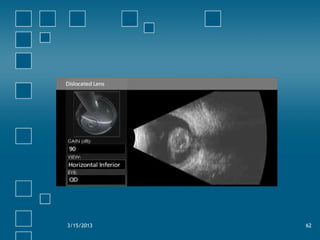

Dislocated lens

• Signals depend on clarity of lens

• Clear lens…Echolucent globular structure

• Brunescent lens…highly reflective with

shadowing